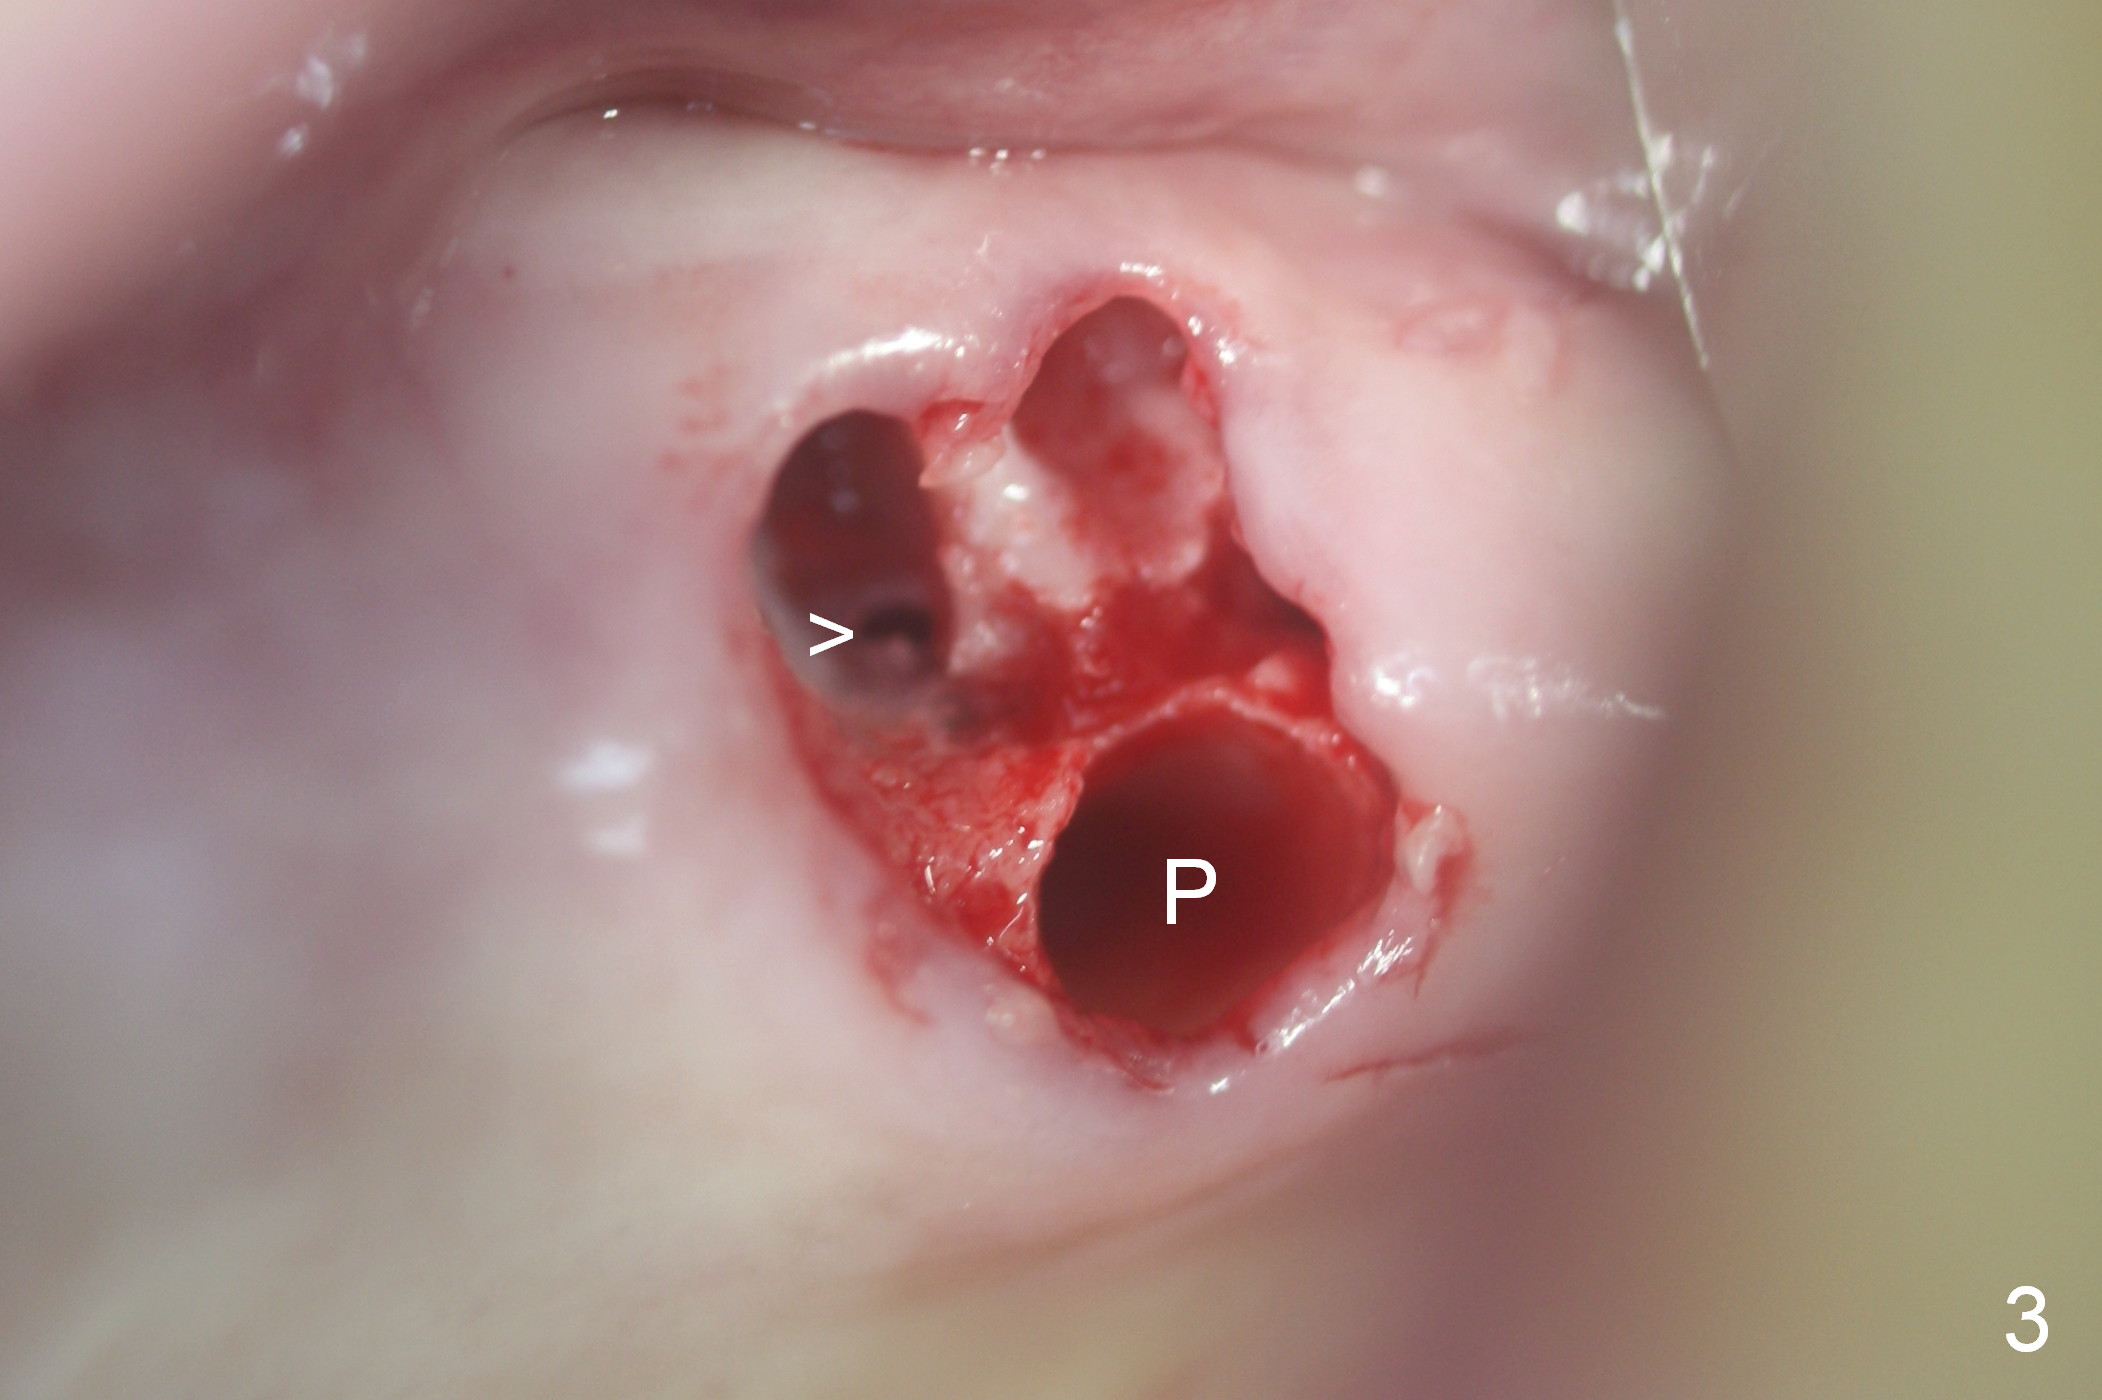

Fig.1,2 show the close relationship of the upper flipper and the residual roots at #15.  Atraumatic extraction using periotomes and surgical sectioning still results in perforation of the mesiobuccal socket (Fig.3 >).  The distobuccal one is shallow, while the septum is small.  It appears that the palatal (Fig.3 P) socket is the most ideal recipient site for the immediate implant and is expanded with Magic Osteotomes until 4.3 mm (Fig.4,5) with the coronal end pushed as buccal as possible.  After placing allograft for sinus lift (Fig.6 >), a 5x11 mm IBS implant is placed with insertion torque ~ 50 Ncm.  A 6x4(3) mm pair abutment is placed, followed by bone graft in the remaining sockets (Fig.6 *) and by Osteogen plug (Fig.7 *).  Finally the socket is sealed by applying acrylic over the abutment (Fig.8).  While the acrylic is setting, the flipper is seated and excess acrylic is removed and pushed away from the flipper (Fig.9).  Advise the patient not to wear the flipper.  If it is being worn, there will be minimal contact between the flipper and the immediate provisional.